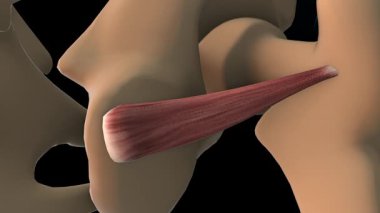

Tıbbi konsept 3 boyutlu illüstrasyon için insan kadın kas anatomisi

KasBileşenlerDorsalfleksörPalmarbrachiiBrevisLongusabdüktöradductorekstansiyonOrasına3d oluşturma3B illüstrasyonCarpiteresdeltoideusDigitorumbrachioradialiskomplikasyondigitiquintipollicisprofundusulnarispronatorPalmarisinterosseiopponenscoracobrachialisKas Anatomisilongus muscleinterossei musclebrevis musclelummbrical muscletricep mucslepollicis musclesuperficialis muscleBenzer İçerikler